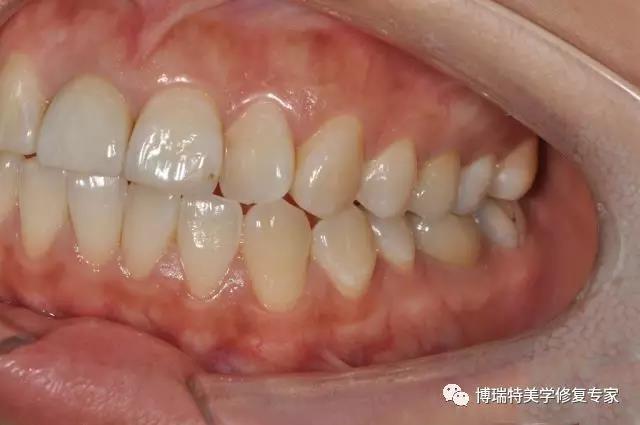

患者:女 23岁

主诉:上颌前牙发黑影响美观,左下后牙原充填物脱落一月余。

检查:11牙体变色,唇侧有充填体,无叩痛,冷热刺激无反应, X示根管阻射,根充物完好,36颌面大面积充填体,部分充填体脱落,无叩痛,冷热刺激无反应,X示根管透射,余牙未见明显异常。

治疗计划:11冠修复,36嵌体修复。